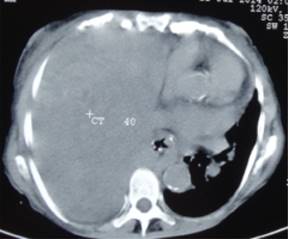

El tamaño de las neoplasias osciló entre 11 y 30 cm en su diámetro mayor, con un promedio de 16.8 cm. En nueve casos (82%), el diagnóstico histológico se hizo después de la resección completa del tumor. En los dos casos restantes (18%) el diagnóstico se confirmó por medio de biopsia cortante con aguja tru-cut en uno de ellos y por biopsia incisional a través de toracotomía limitada en el otro. De los 11 tumores, 10 (90.90%) fueron diagnosticados como TFS de la pleura benignos y el caso restante como TFS de la pleura maligno. Las características de cada uno de ellos se describen en la Tabla 2. Hubo dos muertes atribuibles a la patología, una al décimo día posterior a la toma de biopsia por dificultad respiratoria aguda secundaria al gran tamaño de la masa (Figura 1) y otra en el paciente con tumor maligno, quien falleció durante el seguimiento a los cinco meses de la cirugía, por la progresión de la enfermedad y porque desarrolló el síndrome de Doege-Potter como manifestación paraneoplásica.

Se operaron 10 pacientes, en nueve (90.90%) se logró la resección completa del tumor a través de toracotomía posterolateral, logrando en todos ellos la reexpansión y rehabilitación del hemitórax por el pulmón crónicamente comprimido por el tumor (Figura 2). En los dos (18.18%) casos restantes, uno fue considerado irresecable al encontrar en la toracotomía invasión del tumor a estructuras mediastinales e implantes metastásicos en la cavidad torácica con derrame pleural, por lo que sólo se hizo biopsia incisional. En el caso restante se hizo biopsia cortante percutánea con aguja de tru-cut. Se trataba del tumor más grande de la serie que ocupaba todo el hemitórax y desplazaba el mediastino hacia el lado contralateral en una paciente en muy malas condiciones generales, con franca dificultad respiratoria y sin ninguna posibilidad de ser operada. En esta paciente se optó por una biopsia cortante con aguja de tru-cut, tomando en cuenta que las biopsias por aspiración con aguja fina por lo general no permiten la obtención de material adecuado para diagnóstico, por lo que no se recomiendan.2,11